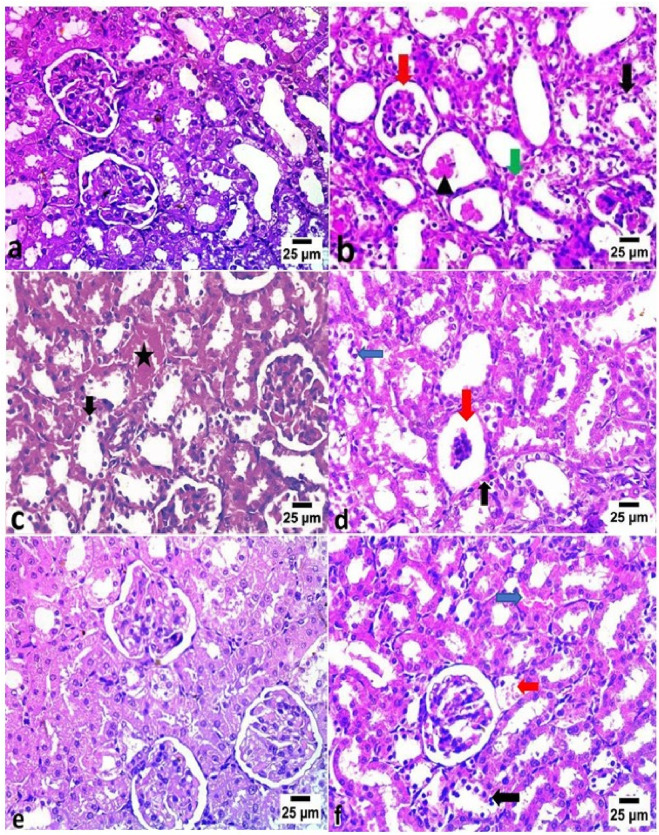

Results: VM administration significantly elevated serum creatinine, urea, and uric acid levels (p < 0.01), increased renal malondialdehyde (MDA), and reduced catalase (CAT) and superoxide dismutase (SOD) activities (p < 0.05). It also induced marked histological changes and increased DNA fragmentation. DF and CE, particularly in combination (Group 5), significantly reduced renal injury, DNA fragmentation, and histopathological alterations. The protective effect followed the order: G5 > G4 > G3 > G2. Furthermore, VM upregulated PARP1, RIP1, KIM1, TNF-α, and IL-1β expression, which were markedly downregulated by DF and CE.